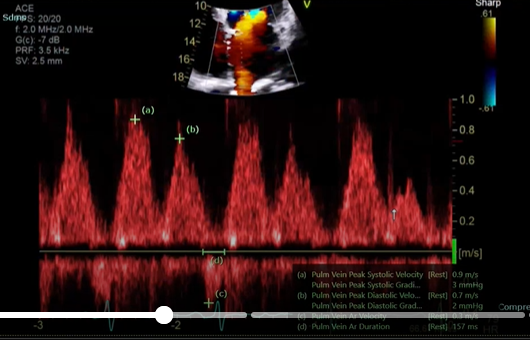

what single is this measurement for what are you going to peak, why would this doppler be important

this measure is for the pulmonary vein

Pulmonary vein peak systolic velocity (peak the S wave)

Peak D wave

peak the velocity of the atrial reversal or atrial duration

This will important when interrogate for MR, If the S wave is shorter than ourt D that is blunting so this coulf point to moderate or severe regurgitation if you see a reversal in these two